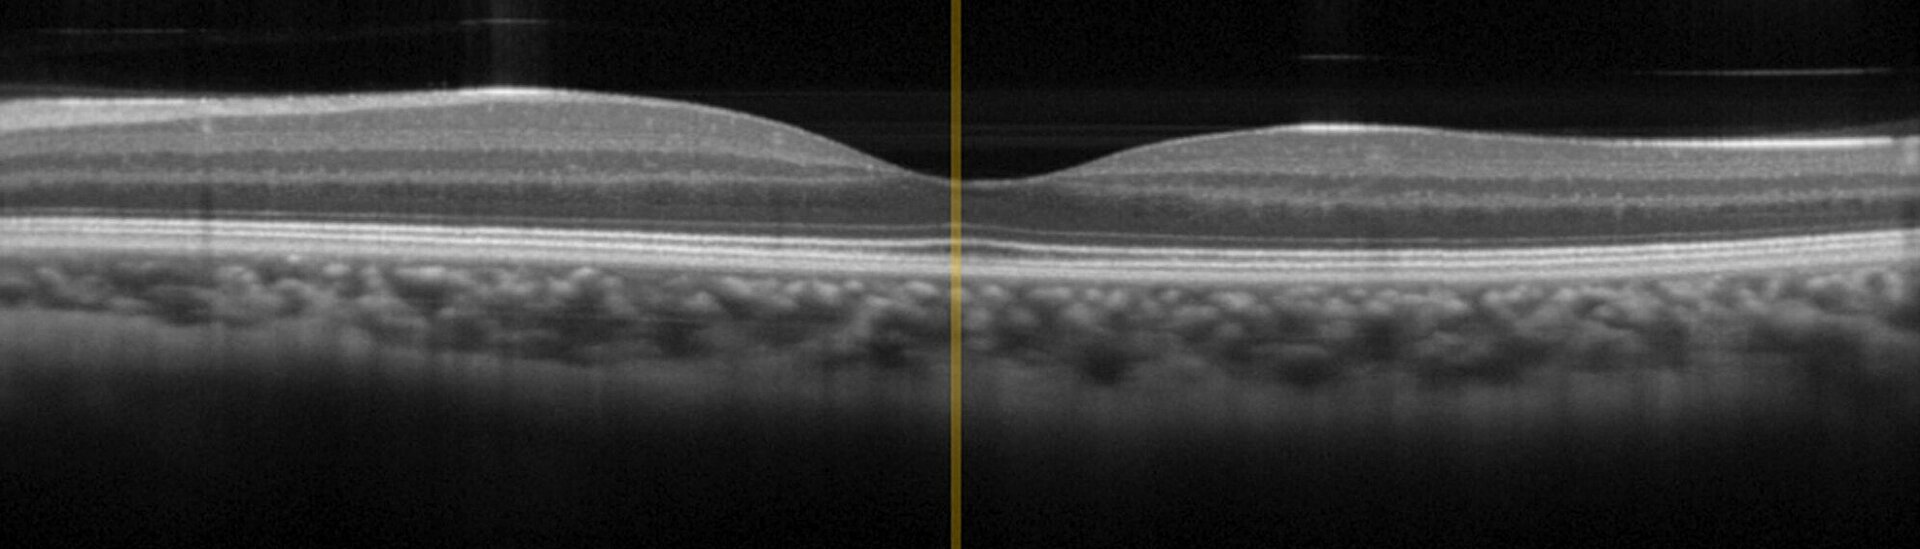

OCT is an interferometric imaging technique based on broadband infrared light in the wavelength range between 0.8 µm and 1.4 µm for optimal tissue penetration. OCT has already achieved "Gold Standard" in ophthalmology but recently also finds growing application in dermatology, for example to diagnose skin cancer. In comparison to conventional invasive diagnostic measures, OCT delivers results faster and reduces side-effects and stress on patients.

The OCT technology uses broadband IR light (in the wavelength region between 800 - 1400 nm due to best penetration in tissue) with short coherence lenght in a Michelson interferometer setup. The signal is a result of the interference from probe- and reference-beam, based on reflections at refractive index boundaries within biological tissue.